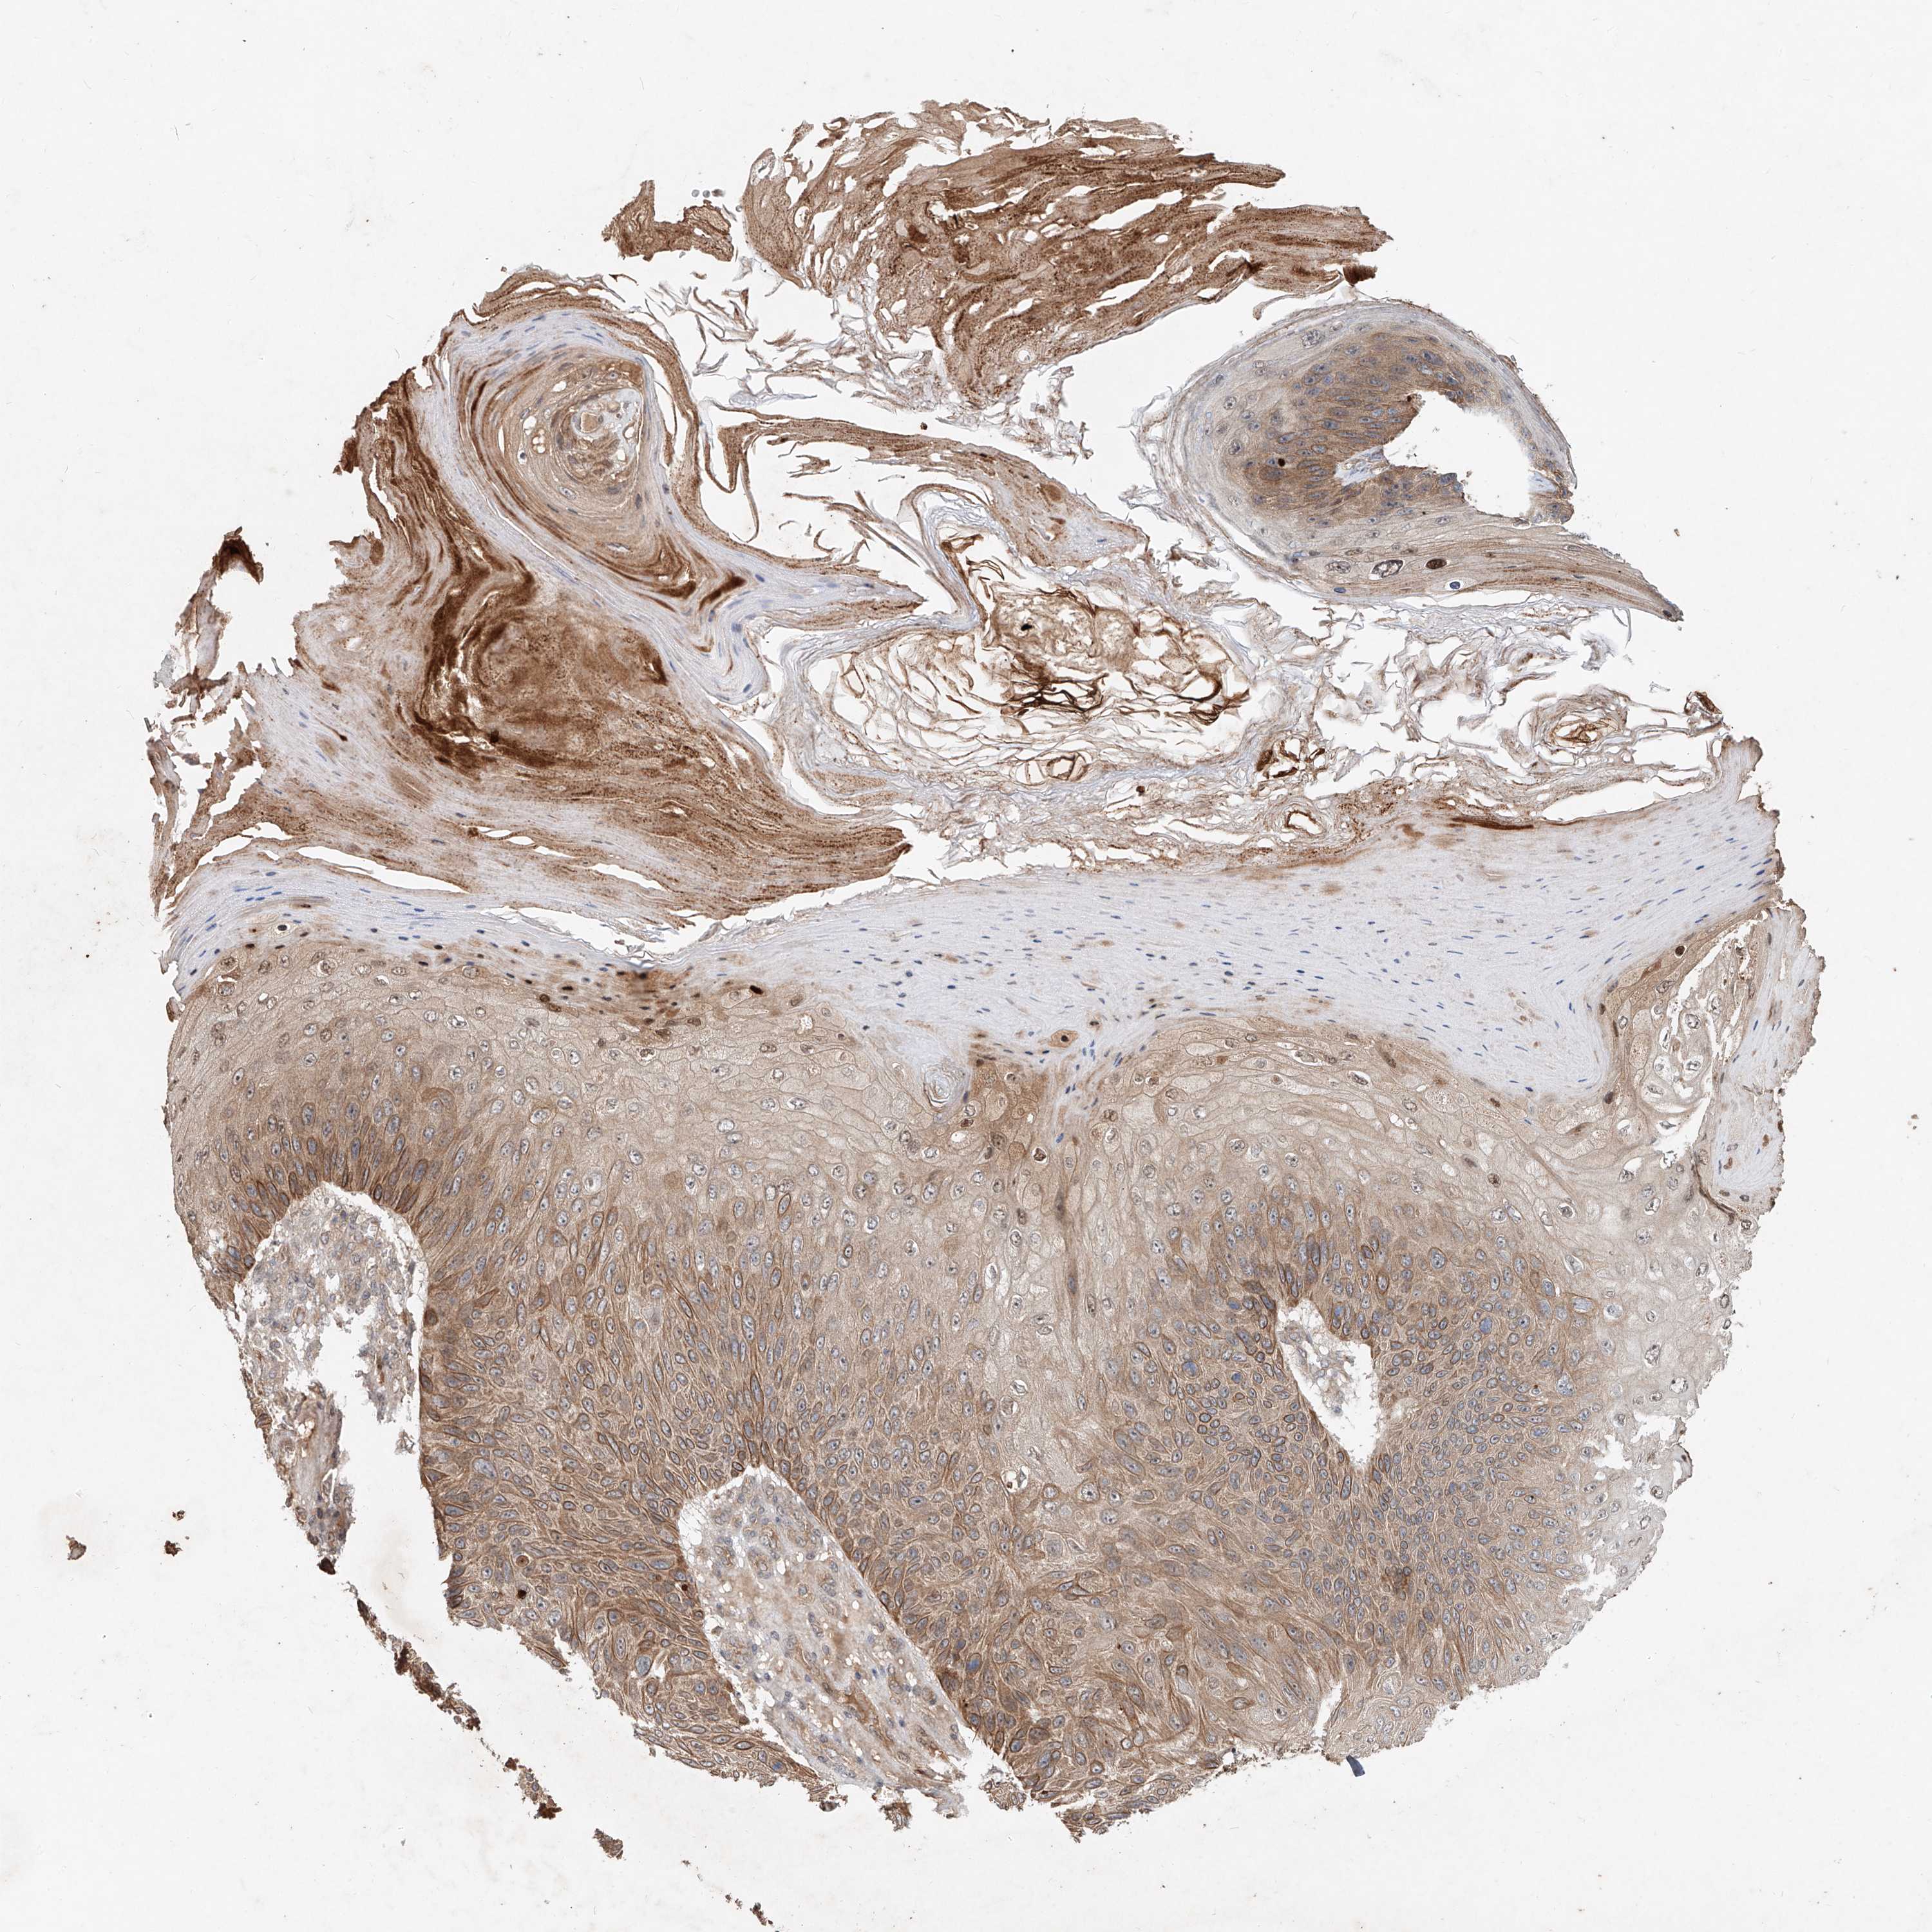

Basal cell and squamous cell cancer

SKIN CANCER - Protein expressioni

A mouse-over function shows sample information and annotation data. Click on an image to view it in a full screen mode. Samples can be filtered based on level of antibody staining by selecting one or several of the following categories: high, medium, low and not detected. The assay and annotation is described here.

Antibody stainingi

Antibody staining in the annotated cell types in the current human tissue is reported as not detected, low, medium, or high, based on conventional immunohistochemistry profiling in selected tissues. This score is based on the combination of the staining intensity and fraction of stained cells.

Each image is clickable and will lead to virtual microscopy that enables deeper exploration of all samples and also displays staining intensity scores, fraction scores and subcellular localization as well as patient and tissue information for each sample.

Antibody HPA029894

Staining

High

Intensity

Strong

Quantity

>75%

Location

Nuclear

Basal cell carcinoma